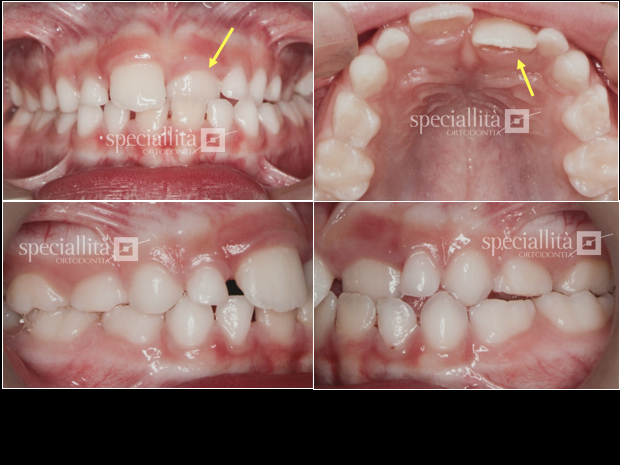

Dentição mista, mordida cruzada anterior envolvendo o incisivo central superior esquerdo (setas), que encontra-se inclinado em direção lingual

Viista frontal e oclusal da correção da mordida cruzada